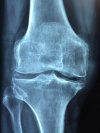

ข้อต่อของหมอนรองกระดูกอ่อนช่วยให้เคลื่อนไหวได้อย่างราบรื่นและง่ายดาย เยื่อหุ้มเซลล์ที่เรียกว่า synovium ผลิตของเหลวหนาที่ช่วยให้กระดูกอ่อนแข็งแรง ไขข้ออักเสบอาจกลายเป็นอักเสบและหนาขึ้นเมื่อมีการสึกหรอของกระดูกอ่อน สิ่งนี้อาจนำไปสู่การอักเสบซึ่งก่อให้เกิดของเหลวภายในข้อต่อทำให้เกิดอาการบวม - และอาจเกิดการพัฒนาของโอเอ

กระดูกอ่อนที่อยู่ติดกันอาจไม่ได้รับการหล่อลื่นที่เพียงพอจากของเหลวไขข้อและกันกระแทกจากกระดูกอ่อน เมื่อพื้นผิวของกระดูกสัมผัสกันโดยตรงมันจะส่งผลให้เกิดความเจ็บปวดและการอักเสบของเนื้อเยื่อรอบ ๆ

เมื่อกระดูกแตกกันอย่างต่อเนื่องพวกมันจะหนาขึ้นและเริ่มมีการสร้าง osteophytes หรือกระดูกสเปอร์